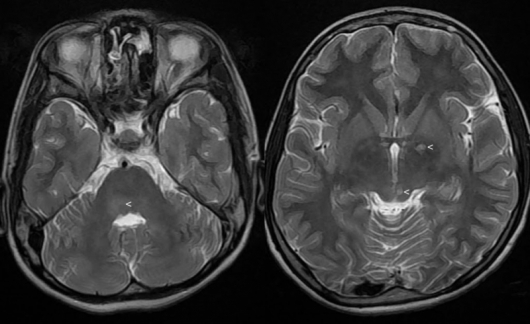

При хронично стресираните хора обаче нивата на кортизол са толкова високи, че мозъкът спира да произвежда неврони, а увеличава производството на миелинови клетки. Миелинът е мастна тъкан, от която се състои бялото мозъчно вещество. Тя ускорява сигналите между невроните. Тези промени обаче може да доведат до шизофрения или друго умствено разстройство.